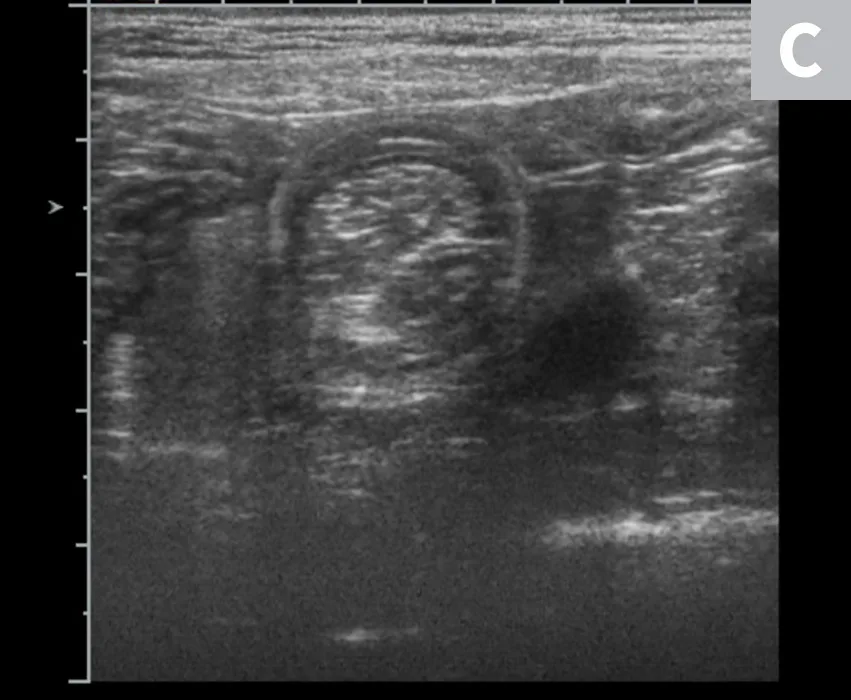

Diagnostic steps include a complete physical examination, abdominal radiography, and abdominal ultrasonography (or a contrast study if ultrasonography equipment is not available). On physical examination, a thickened tubular structure may be palpated in the abdomen, which may be painful for the patient. Abdominal radiographs commonly reveal a fluid- or gas-filled bowel consistent with a mechanical obstruction.2 Abdominal ultrasonography is often the most helpful preoperative diagnostic tool (Figure 1); the finding of multiple hyperechoic and hypoechoic concentric rings in transverse sections, parallel lines in longitudinal sections, or both is diagnostic of intestinal intussusception.4 Abdominal radiography with contrast media (ie, barium) can outline the intussusceptum in the lumen of the intussuscipiens, or the contrast can appear as a ribbon-like structure in the intussusceptum.2

FIGURE 1

Abdominal ultrasound images of a dog with jejuno-jejunal intussusception secondary to an intestinal sarcoma (A), a dog with ileocolic intussusception (B), and a dog with jejuno-jejunal intussusception without an identifiable underlying cause (C)